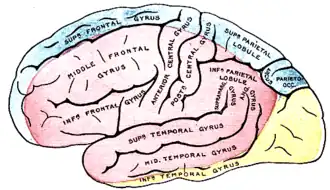

На фоне общемозговых симптомов инсульта появляются очаговые симптомы поражения головного мозга. Клиническая картина у каждого конкретного больного человека определяется тем, какой участок мозга пострадал из-за повреждения кровоснабжающего его сосуда.

Зоны кровоснабжения: Arteria cerebri anterior (синий цвет) |

Нарушения кровотока в бассейне внутренней сонной артерии (ВСА)

Закупорка ВСА может возникать в её начале (области бифуркации общей сонной артерии), каротидном сифоне и супраклиноидной части (чаще вследствие образования тромба на месте атеросклеротической бляшки) и протекать бессимптомно при достаточном коллатеральном кровообращении через артериальный круг большого мозга и другие анастомозы. При недостаточном коллатеральном кровообращении или в случаях артерио-артериальной эмболии возникают геми- или моноплегия, афазия и другие расстройства[16]:237. Развитие монокулярной слепоты на одной стороне и гемипареза на противоположной (окулопирамидный синдром) — характерно (патогномонично) для стеноза или закупорки ВСА[31].

Окклюзия передней мозговой артерии (ПМА)

Если закупорка возникла до отхождения передней соединительной артерии, то она может протекать бессимптомно вследствие коллатерального кровотока из противоположной ПМА[16]:238. Инфаркт при окклюзии ПМА проявляется контрлатеральным параличом нижней конечности и хватательным рефлексом. Характерны спастичность с непроизвольным сопротивлением пассивным движениям, абулия, абазия, персеверации и недержание мочи[31].

Окклюзия средней мозговой артерии (СМА)

Для окклюзии СМА характерны контрлатеральные гемиплегия, гемигипестезия, гомонимная гемианопсия. Наблюдается контрлатеральный парез взора. При поражении доминантного полушария развивается афазия, при поражении недоминантного — апраксия, агнозия, асоматогнозия и анозогнозия.

При окклюзии отдельных ветвей СМА возникают парциальные синдромы: моторная афазия в сочетании с контрлатеральным парезом верхней конечности и лицевого нерва при поражении верхних ветвей; сенсорная афазия при поражении нижних ветвей[31].

Окклюзия задней мозговой артерии (ЗМА)

При окклюзии задней мозговой артерии возможно развитие одного из двух синдромов: сочетание гомонимной гемианопсии с амнезией, дислексией (без дисграфии) и лёгкого контрлатерального гемипареза с гемианестезией; либо сочетание поражения ипсилатерального глазодвигательного нерва с контрлатеральными непроизвольными движениями и контрлатеральной гемиплегией или атаксией[31].